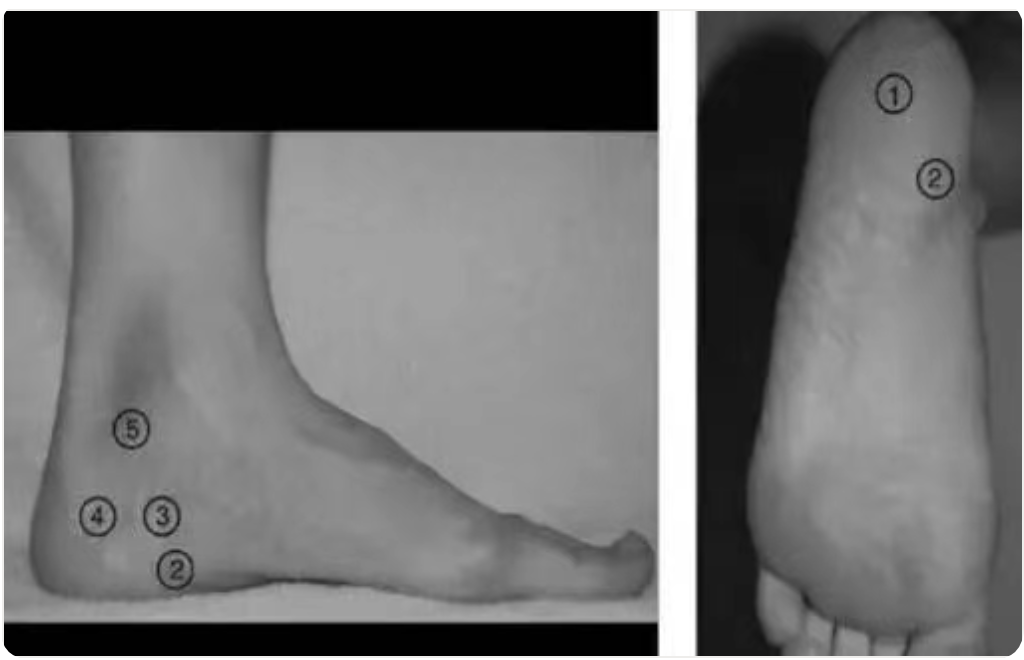

五种足跟痛的痛点及定位图1示:

图 1 五种足跟痛的压痛点和位置:①足跟垫萎缩 ②足底筋膜炎 ③巴克斯特神经卡压综合症 ④跟骨压缩性骨折 ⑤踝管综合症